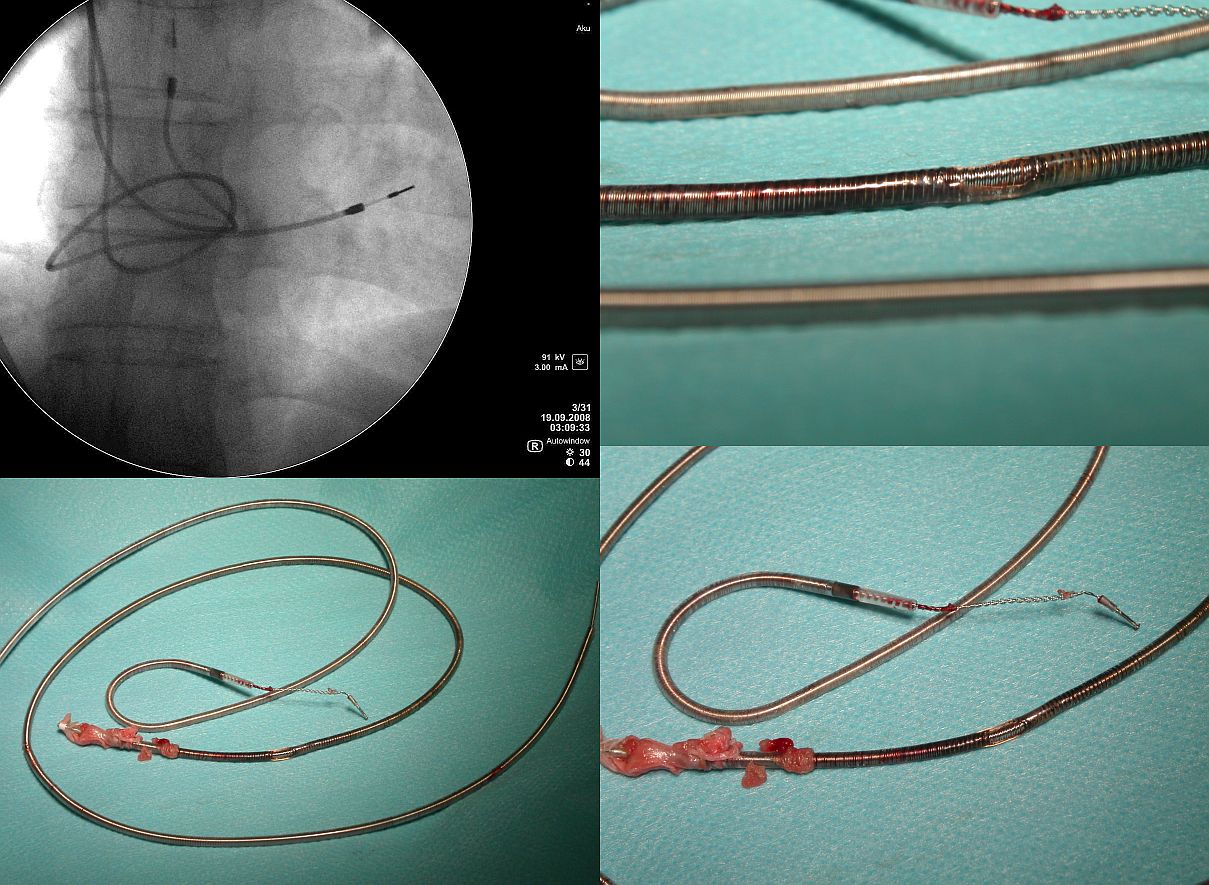

- Objawy "elektryczne". W oparciu o nasze

wieloletnie doświadczenia uważamy, że zależą one od

typu elektrod i są inne w elektrodach defibrylujących

inne w elektrodach stymulatorowych jednobiegunowych a zupełnie

inne w elektrodach stymulatorowych dwubiegunowych.

A. W elektrodach stymulatorowych jednobiegunowych

przetarcie osłonki manifestuje się postępującym

wzrostem progu stymulacji i spadkiem oporności aż do

wartości poniżej 200 omów. Możliwy jest też odbiór

potencjałów z miejsca przetarcia np. potencjału

przedsionkowego przez elektrod komorową jak również

symulacja ściany serca w miejscu przetarcia. Jednak

perforacja osłonki elektrody jednobiegunowej manifestuje

się zwykle utratą skuteczności stymulacji; pozostałe

zjawiska mają marginalne znaczenie.

B. W elektrodach stymulatorowych dwubiegunowych przetarcie

osłonki zewnętrznej pozostaje przez bardzo długi czas

bezobjawowe lub skąpoobjawowe. W konfiguracji

jednobiegunowej nie można wykryć żadnych nieprawidłowości.

W konfiguracji dwubiegunowej spadek oporności jest

niewielki (rzędu 100-200 omów, np. z 600 do 400 omów) i

umyka obserwacji. Tak niewielki spadek oporności nie

zmienia istotnie progu stymulacji a stymulacja (anodalna)

z miejsca odsłonięcia spirali zewnętrznej elektrody

jest zjawiskiem marginalnym i czasem daje się zauważyć

jedynie przy stymulacji z maksymalną energią impulsu.